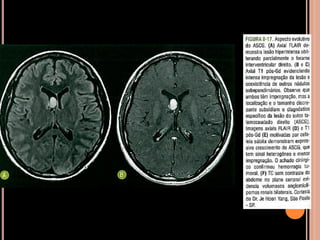

NF1 - RM

Gliomas de via óptica:

Espessamento da bainha/nervo de aspecto

tubular/fusiforme ou globular

Hipossinal em T1 e hipersinal em T2

Impregnação homogênea pelo Gd;

Ocasionalmente dilatação do espaço subaracnoideo

perineural;

Pode haver extensão ao quiasma óptico e aos corpos

geniculados laterais;

Gliomas do tronco encefálico:

Maioria benigno, podendo estabilizar-se ou regredir

Isossinal em T1 e hipersinal em T2;

NF1

Gliomas do teto mesencefálico:

 Pode determinar hidrocefalia pela obstrução de

aqueduto;

 Iso ou hipossinal em T1 e hipersinal em T2;

 Usualmente sem impregnação pelo Gd nos tu

pequenos;

Área de vacuolização de mielina

 Focos hiperintensos em T2 e no FLAIR em núcleos

da base, cápsula interna, tronco encefálico e

cerebelo;

 Mais comum no globo pálido, geralmente bilateral;

Vacuolização de mielina

 Aparecimento geralmente aos 3 anos  aumenta

até os 12 anos  tendência a regredir;

 Raro observar após os 20 anos de idade;